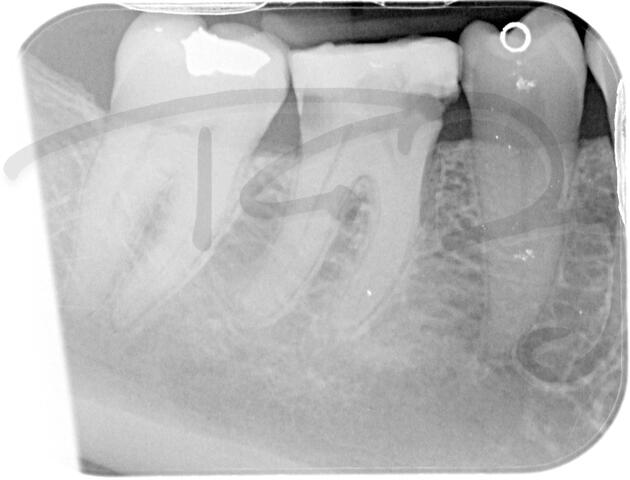

I am pleased to take endodontic referrals. Curved canals >30 degrees and potentially greater than 50 degrees can be negotiated. Sclerosed canals accessed. Post spaces prepared and the patient returned to you ready to restore.In most cases existing crowns, bridges and veneers can be retained with the endodontic access aesthetically restored after the full canal network has been treated.In the first instance I would prefer a radiograph and a brief list of patient expectations and a tooth history.